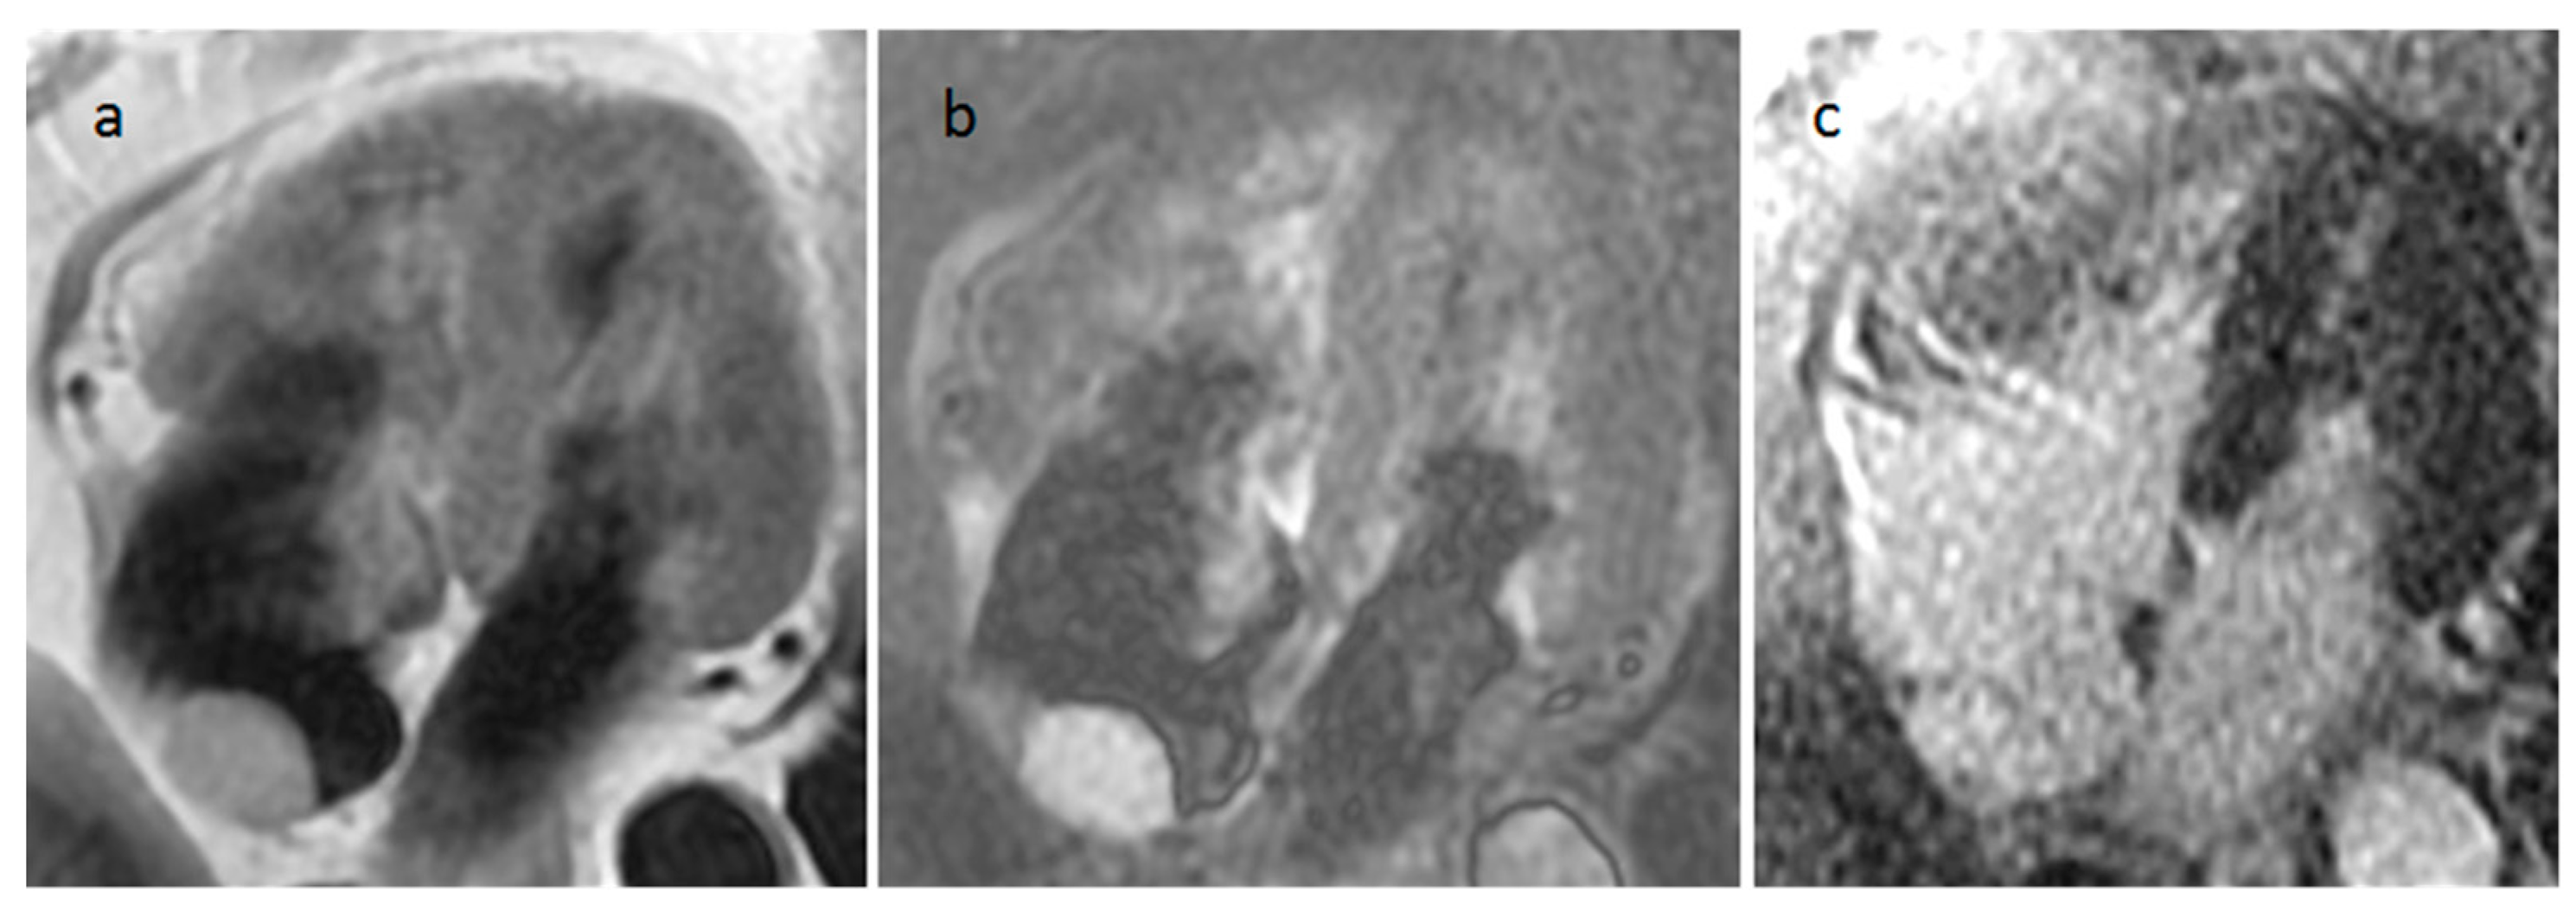

5.3. Primary Cardiac Lymphoma

| Lymphoma | Adulthood, Immunocompromised | RA, RV, pericardium | Pericardial effusion, flow obstruction/heart failure | Uniform, infiltrative, extend along the epicardial surfaces of the heart, encase adjacent vascular structures, hypermetabolic on PET | Pericardial effusion. Tumor might be detected with homogeneous echogenicity. | Pericardial effusion. Normal to low attenuation, heterogeneous and mild contrast enhancement | Iso-hypo T1w, Iso-hyper T2w, none-minimal homogeneous LGE. Evident diffusion restriction |